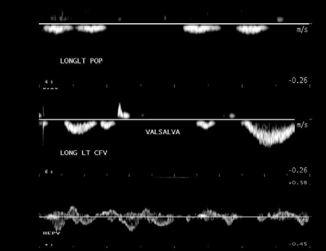

what do these waveforms depict?

resp phasicity

valsalva

cardiac pulsatility

normal or abn

abn → incomp vein